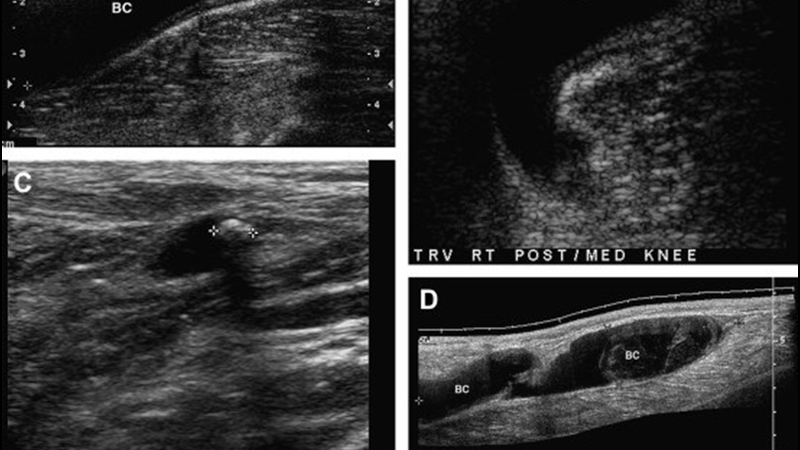

Hình ảnh siêu âm tĩnh mạch là một phương pháp hình ảnh y tế không xâm lấn, sử dụng sóng âm thanh để tạo ra hình ảnh bên trong cơ thể. Trong quá trình này, sóng âm thanh được tạo ra từ đầu dò và truyền qua gel được đặt trực tiếp lên da, sau đó được thu lại bởi đầu dò.

Các sóng âm này được phân tích bởi máy tính để tạo ra hình ảnh, không sử dụng bức xạ như chụp X-quang. Do hình ảnh được tạo ra trong thời gian thực, nó có thể hiển thị cấu trúc và chuyển động của các cơ quan bên trong cơ thể, cũng như lưu lượng máu trong các mạch máu.

Siêu âm tĩnh mạch là một công cụ quan trọng giúp bác sĩ chẩn đoán và điều trị các bệnh lý liên quan đến tĩnh mạch. Đặc biệt, siêu âm Doppler màu thường được sử dụng để đánh giá chuyển động của máu trong các động mạch và tĩnh mạch, cung cấp thông tin về lưu lượng máu trong cơ thể.